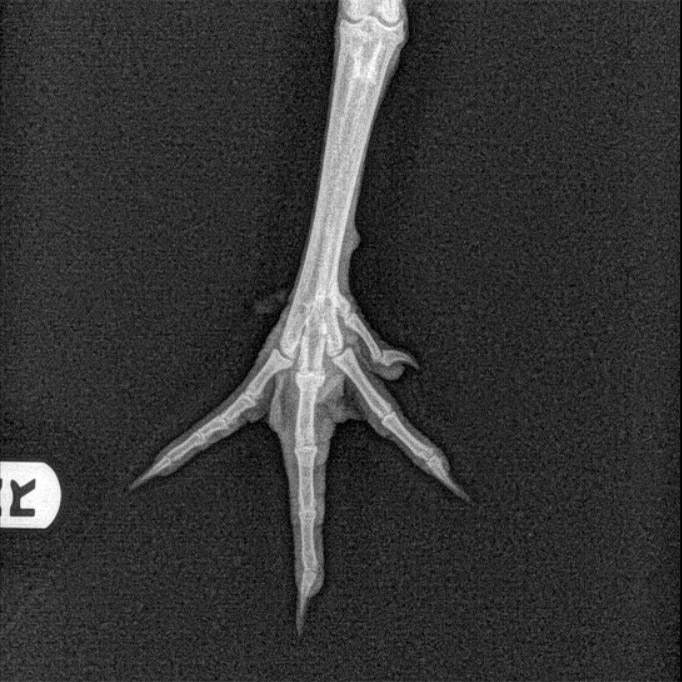

X Ray Of A Chicken Leg . • with the patient in this position, an extended leg vd/craniocaudal projection of the pelvic limbs can be imaged separately, if desired. However, it’s important to use them appropriately. See examples of normal and abnormal radiographs of the coelomic cavity, pelvic limbs, and pectoral limbs. The limb closest to the cassette is always. Learn how to perform radiographic examination of avian patients, including positioning, technique, and anesthesia. Learn how to check for signs of a broken leg in your chicken, such as swelling, bruising, and limited movement. Find out how to make a simple leg brace, give pain relief, and provide care until the leg heals. If you can read chicken xrays and you have any thoughts on alternative diagnosis or treatment please advise me. We love sophie and just want to do. The legs are extended ventrally away from the body wall and fastened with tape. The dependent leg is positioned cranial to the other leg. Here are some key points to consider:

X Ray Of A Chicken Leg Learn how to perform radiographic examination of avian patients, including positioning, technique, and anesthesia. Here are some key points to consider: The limb closest to the cassette is always. If you can read chicken xrays and you have any thoughts on alternative diagnosis or treatment please advise me. Learn how to check for signs of a broken leg in your chicken, such as swelling, bruising, and limited movement. However, it’s important to use them appropriately. The dependent leg is positioned cranial to the other leg. See examples of normal and abnormal radiographs of the coelomic cavity, pelvic limbs, and pectoral limbs. The legs are extended ventrally away from the body wall and fastened with tape. Find out how to make a simple leg brace, give pain relief, and provide care until the leg heals. We love sophie and just want to do. • with the patient in this position, an extended leg vd/craniocaudal projection of the pelvic limbs can be imaged separately, if desired. Learn how to perform radiographic examination of avian patients, including positioning, technique, and anesthesia.

Radiography and Ultrasonography in the Backyard Poultry and Waterfowl X Ray Of A Chicken Leg The dependent leg is positioned cranial to the other leg. The legs are extended ventrally away from the body wall and fastened with tape. If you can read chicken xrays and you have any thoughts on alternative diagnosis or treatment please advise me. See examples of normal and abnormal radiographs of the coelomic cavity, pelvic limbs, and pectoral limbs. •. X Ray Of A Chicken Leg.